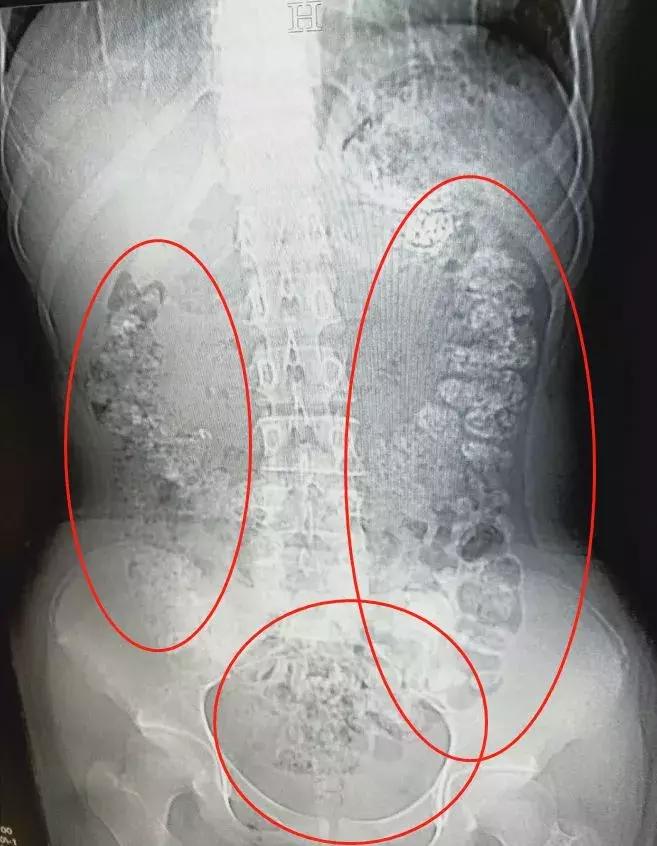

急诊科医生张楼炜对朱丽进行了初步检查,发现她肚子鼓鼓的,就让她去做了腹部CT,谁知道,拍出来的片子让张楼炜大吃一惊,患者胃部、横结肠、升结肠、降结肠、乙状结肠,一直到肛门,全是颗粒状阴影,足有百余颗。

14岁女孩喝了珍珠奶茶后,五天没有排便,还肚子疼,CT检查发现胃肠道,布满一颗颗圆圆的高密度阴影,肠胃道里全是“珍珠”